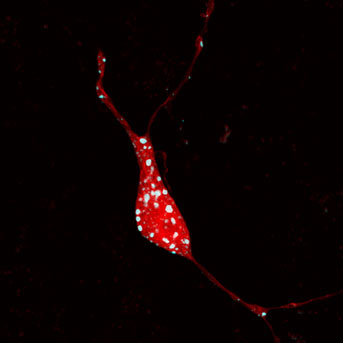

The researchers employed several tools to track brain pathways and specific areas of neurons involved in specific behaviors, including imaging techniques and social strategy behavioral models. Two populations of neurons were identified in the brain’s ventral pallidum region (part of the basal ganglia) as key to underlying depressive behavior.